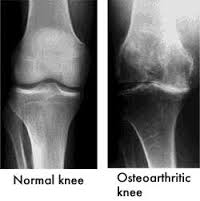

- X-rays: To identify changes in bone structure and joint space narrowing.

Osteoarthritis is the most prevalent form of knee arthritis, often referred to as “wear-and-tear” arthritis. This degenerative joint disease occurs when the cartilage cushioning the ends of the bones in the knee gradually deteriorates. As the cartilage wears away, the bones begin to rub against each other, leading to pain, swelling, and decreased joint function.

Knee arthritis can manifest in various forms, each with unique characteristics. The two most common types affecting the knee are Osteoarthritis and Inflammatory Arthritis: